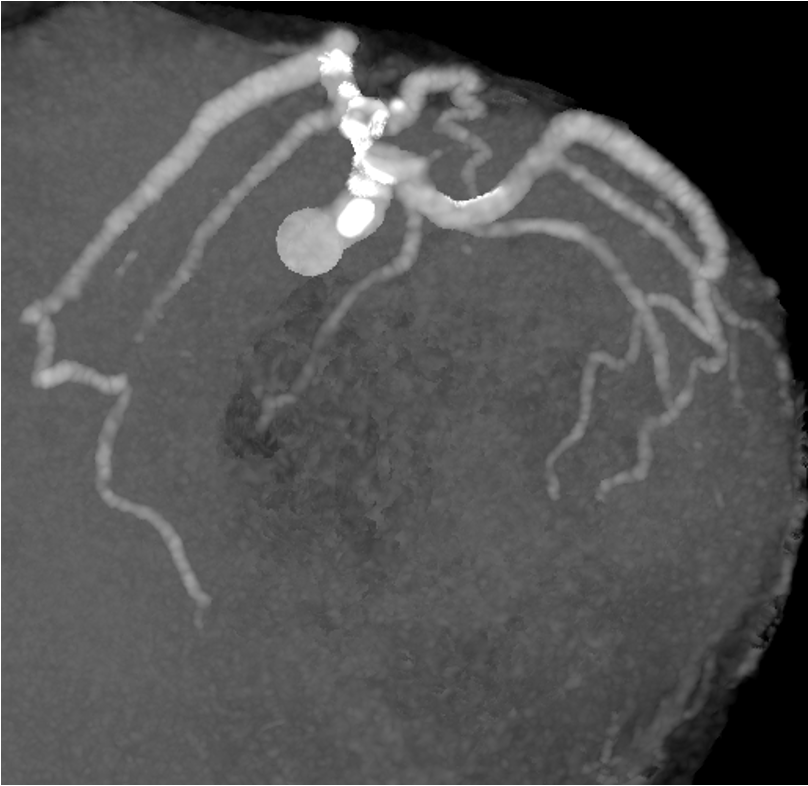

LCA CAG

-

RCA CAG

LAD FFR & Dx RFR